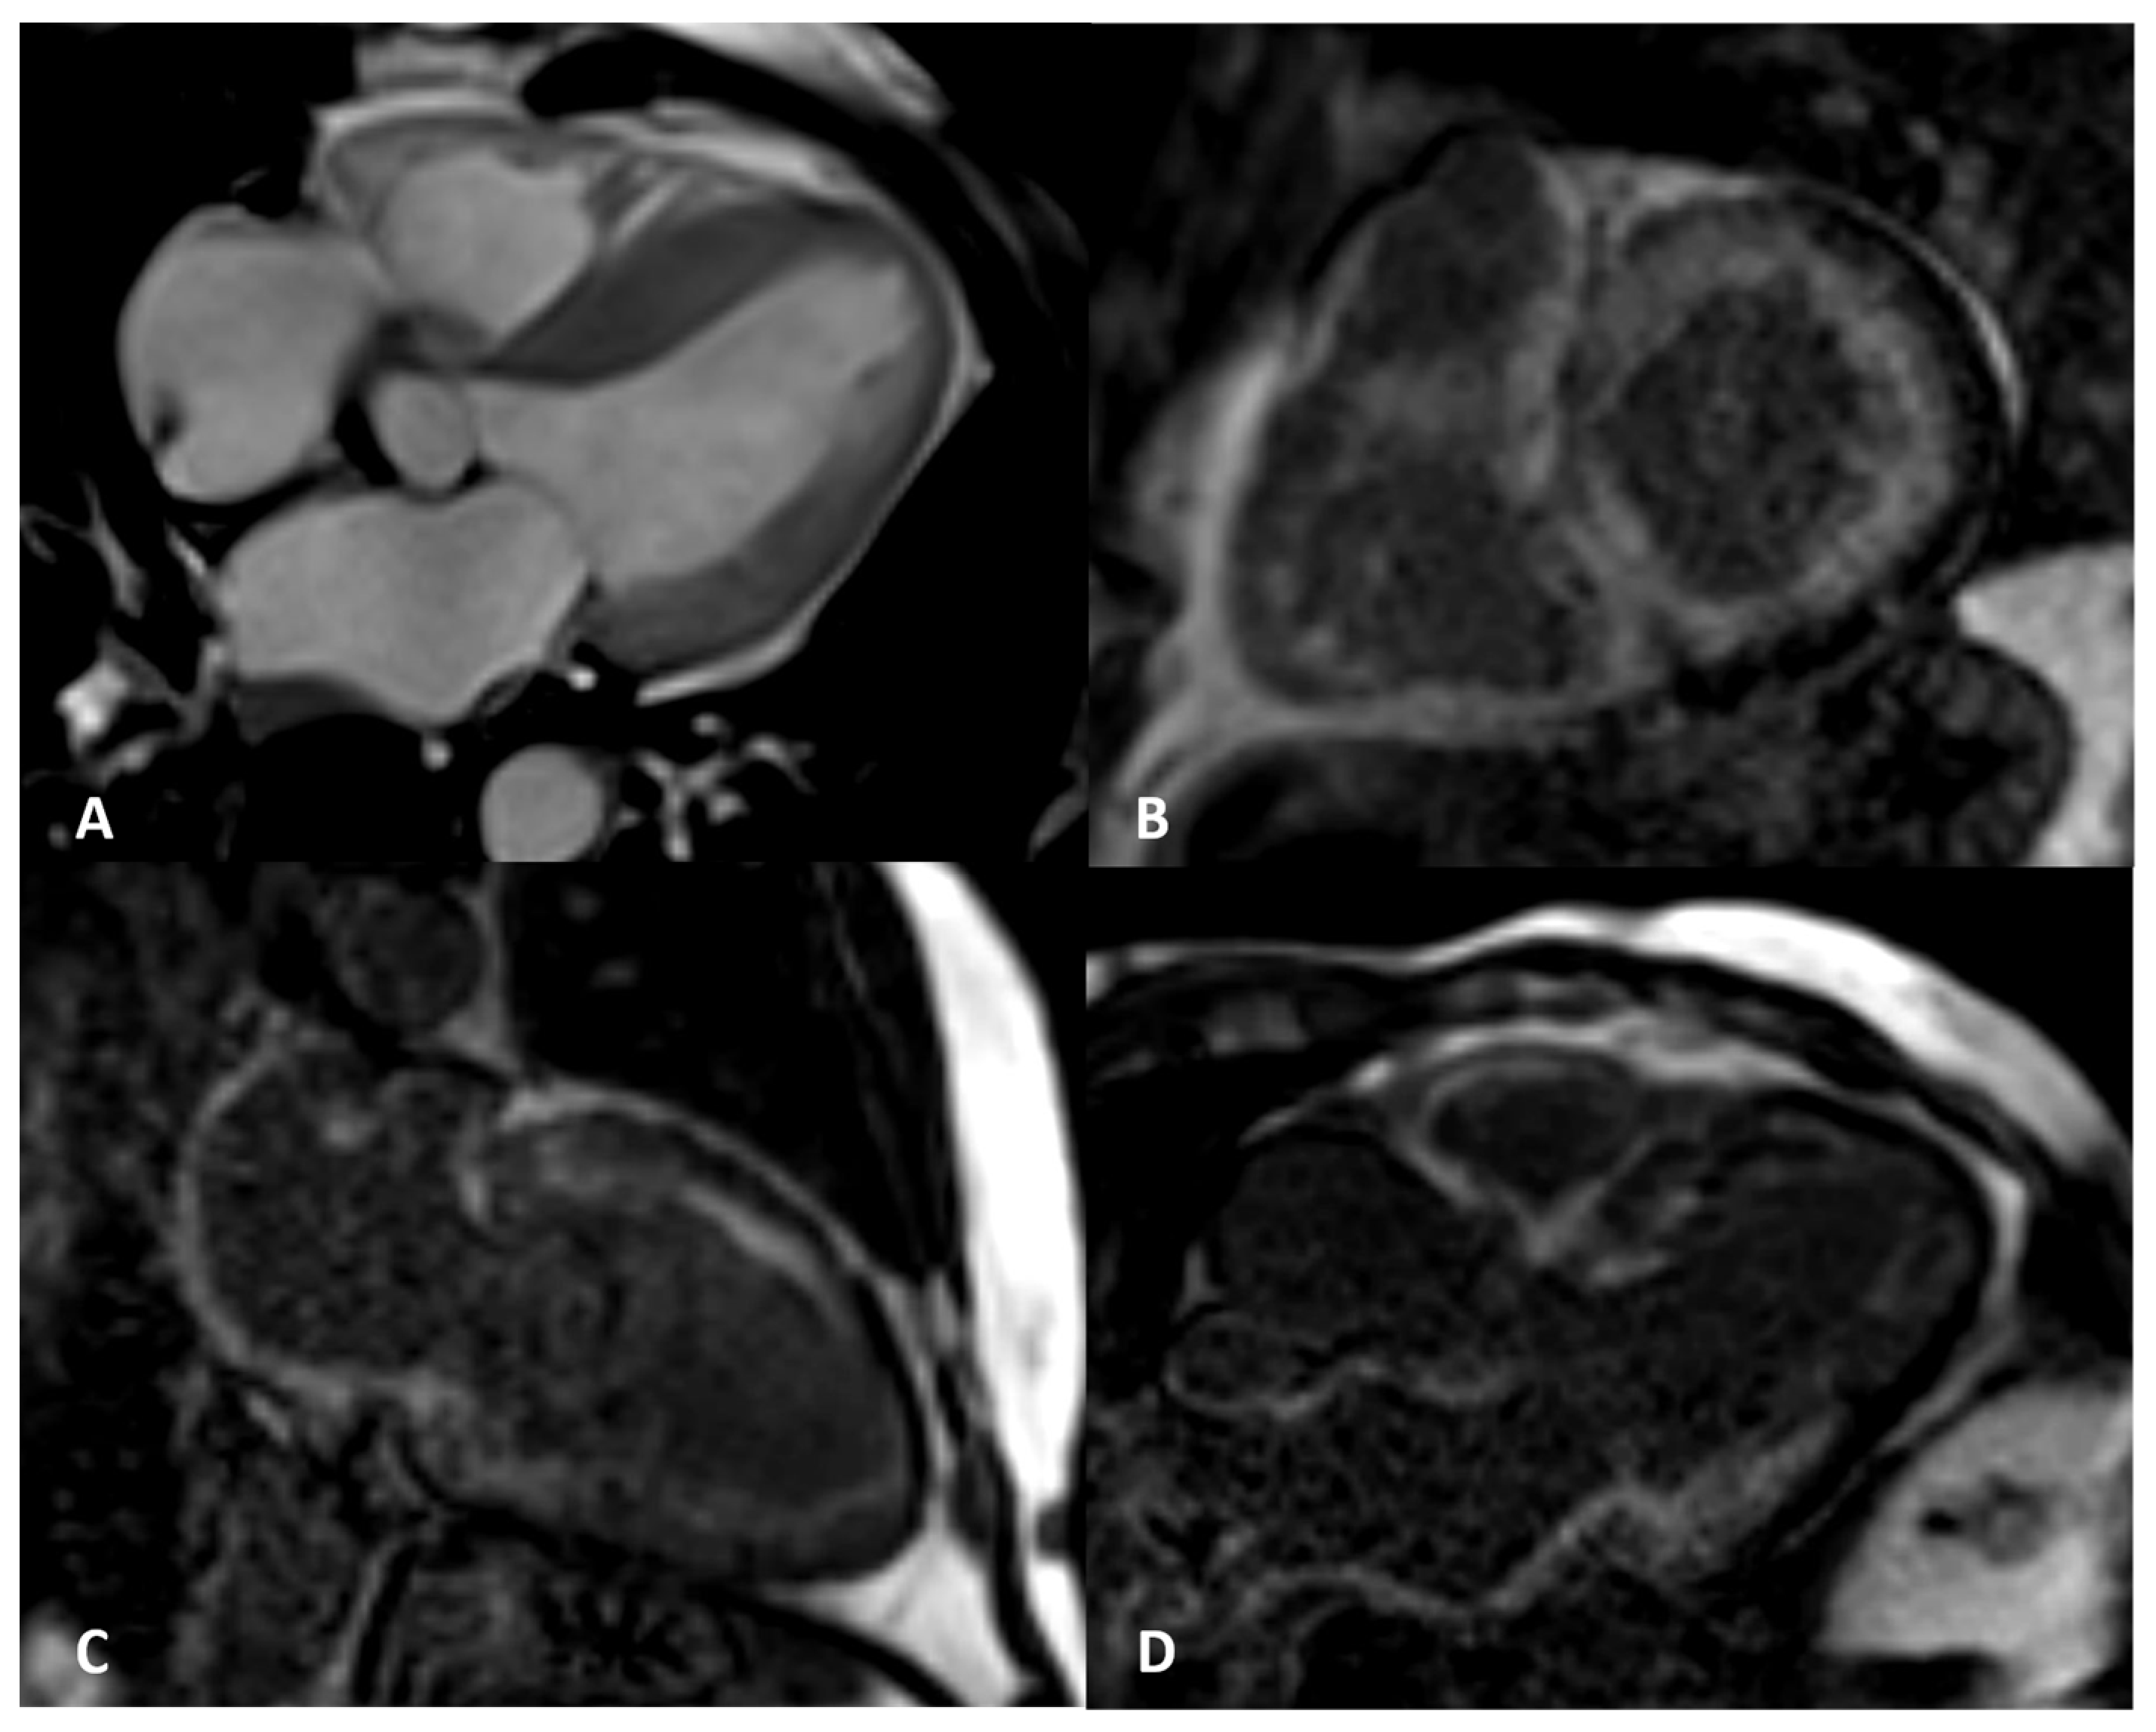

Figure 2.

AL amyloidosis confirmed by endomyocardial biopsy. An elderly patient with NYHA III heart failure and 42% LVEF. Four-chamber balanced-steady state free precession (b-SSFP) MRI (A) shows symmetric thickening of the left ventricle with the septum maximally measuring 25 mm. Circumferential subendocardial LV LGE in two-chamber short (B) and long axes (C) and three-chamber b-SSFP (D); QALE score 12.

Figure 3.

ATTR elderly patient. Transmural semicircumferential LGE pattern and symmetric thickening of the left ventricle with septum maximally measuring 21 mm.